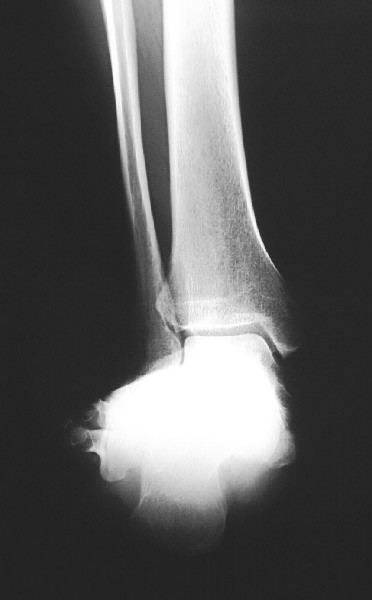

Pertinent Points On Diagnostic Imaging

Assess standard weightbearing views (AP, lateral and oblique views of the foot and ankle) for degenerative changes and angular deformity. Evaluating ankle films helps in ruling out a valgus deformity within the ankle joint. One can measure the talo-first metatarsal angle on AP and lateral foot radiographs. Obtaining a hindfoot alignment view and long leg calcaneal axial views can help in determining the level of valgus deformity (STJ vs. AJ vs. calcaneus). When assessing adolescent patients, clinicians should rule out tarsal coalitions. Obtaining a MRI can be helpful to rule out fibrous or cartilaginous coalitions in these patients. Advanced imaging is also beneficial to evaluate joint integrity when deciding between joint sparing procedures or an arthrodesis.